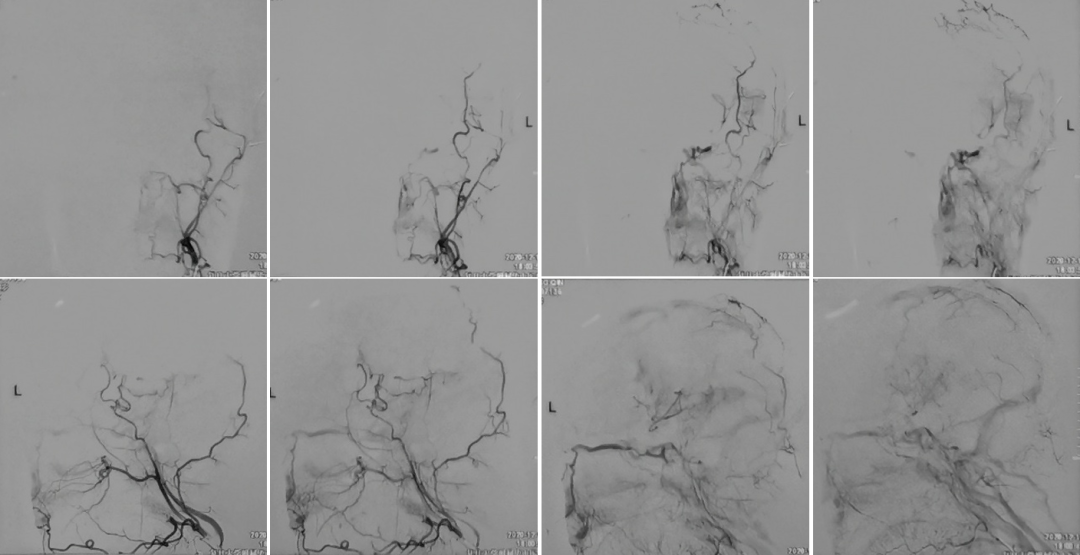

今天为大家分享的是,由复旦大学附属华山医院顾宇翔教授和倪伟医师带来的:巨大复杂颈内动脉分叉部动脉瘤一例,欢迎阅读、分享。

术前诊断: